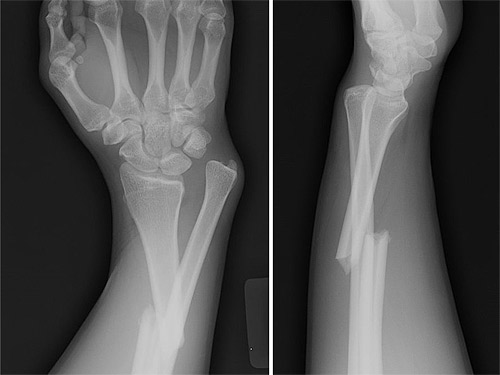

Presentaba una fractura similar a la de esta radiografía

La lesión de Julián en el brazo izquierdo, como lo indicó el diagnóstico médico, consistió en la fractura del tercio medio del hueso radio, con desplazamiento del mismo. Por eso, esta misms mañana los médicos que lo atienden decidieron que era necesaria la operación.

La lesión de Julián en el brazo izquierdo, como lo indicó el diagnóstico médico, consistió en la fractura del tercio medio del hueso radio, con desplazamiento del mismo. Por eso, esta misms mañana los médicos que lo atienden decidieron que era necesaria la operación.